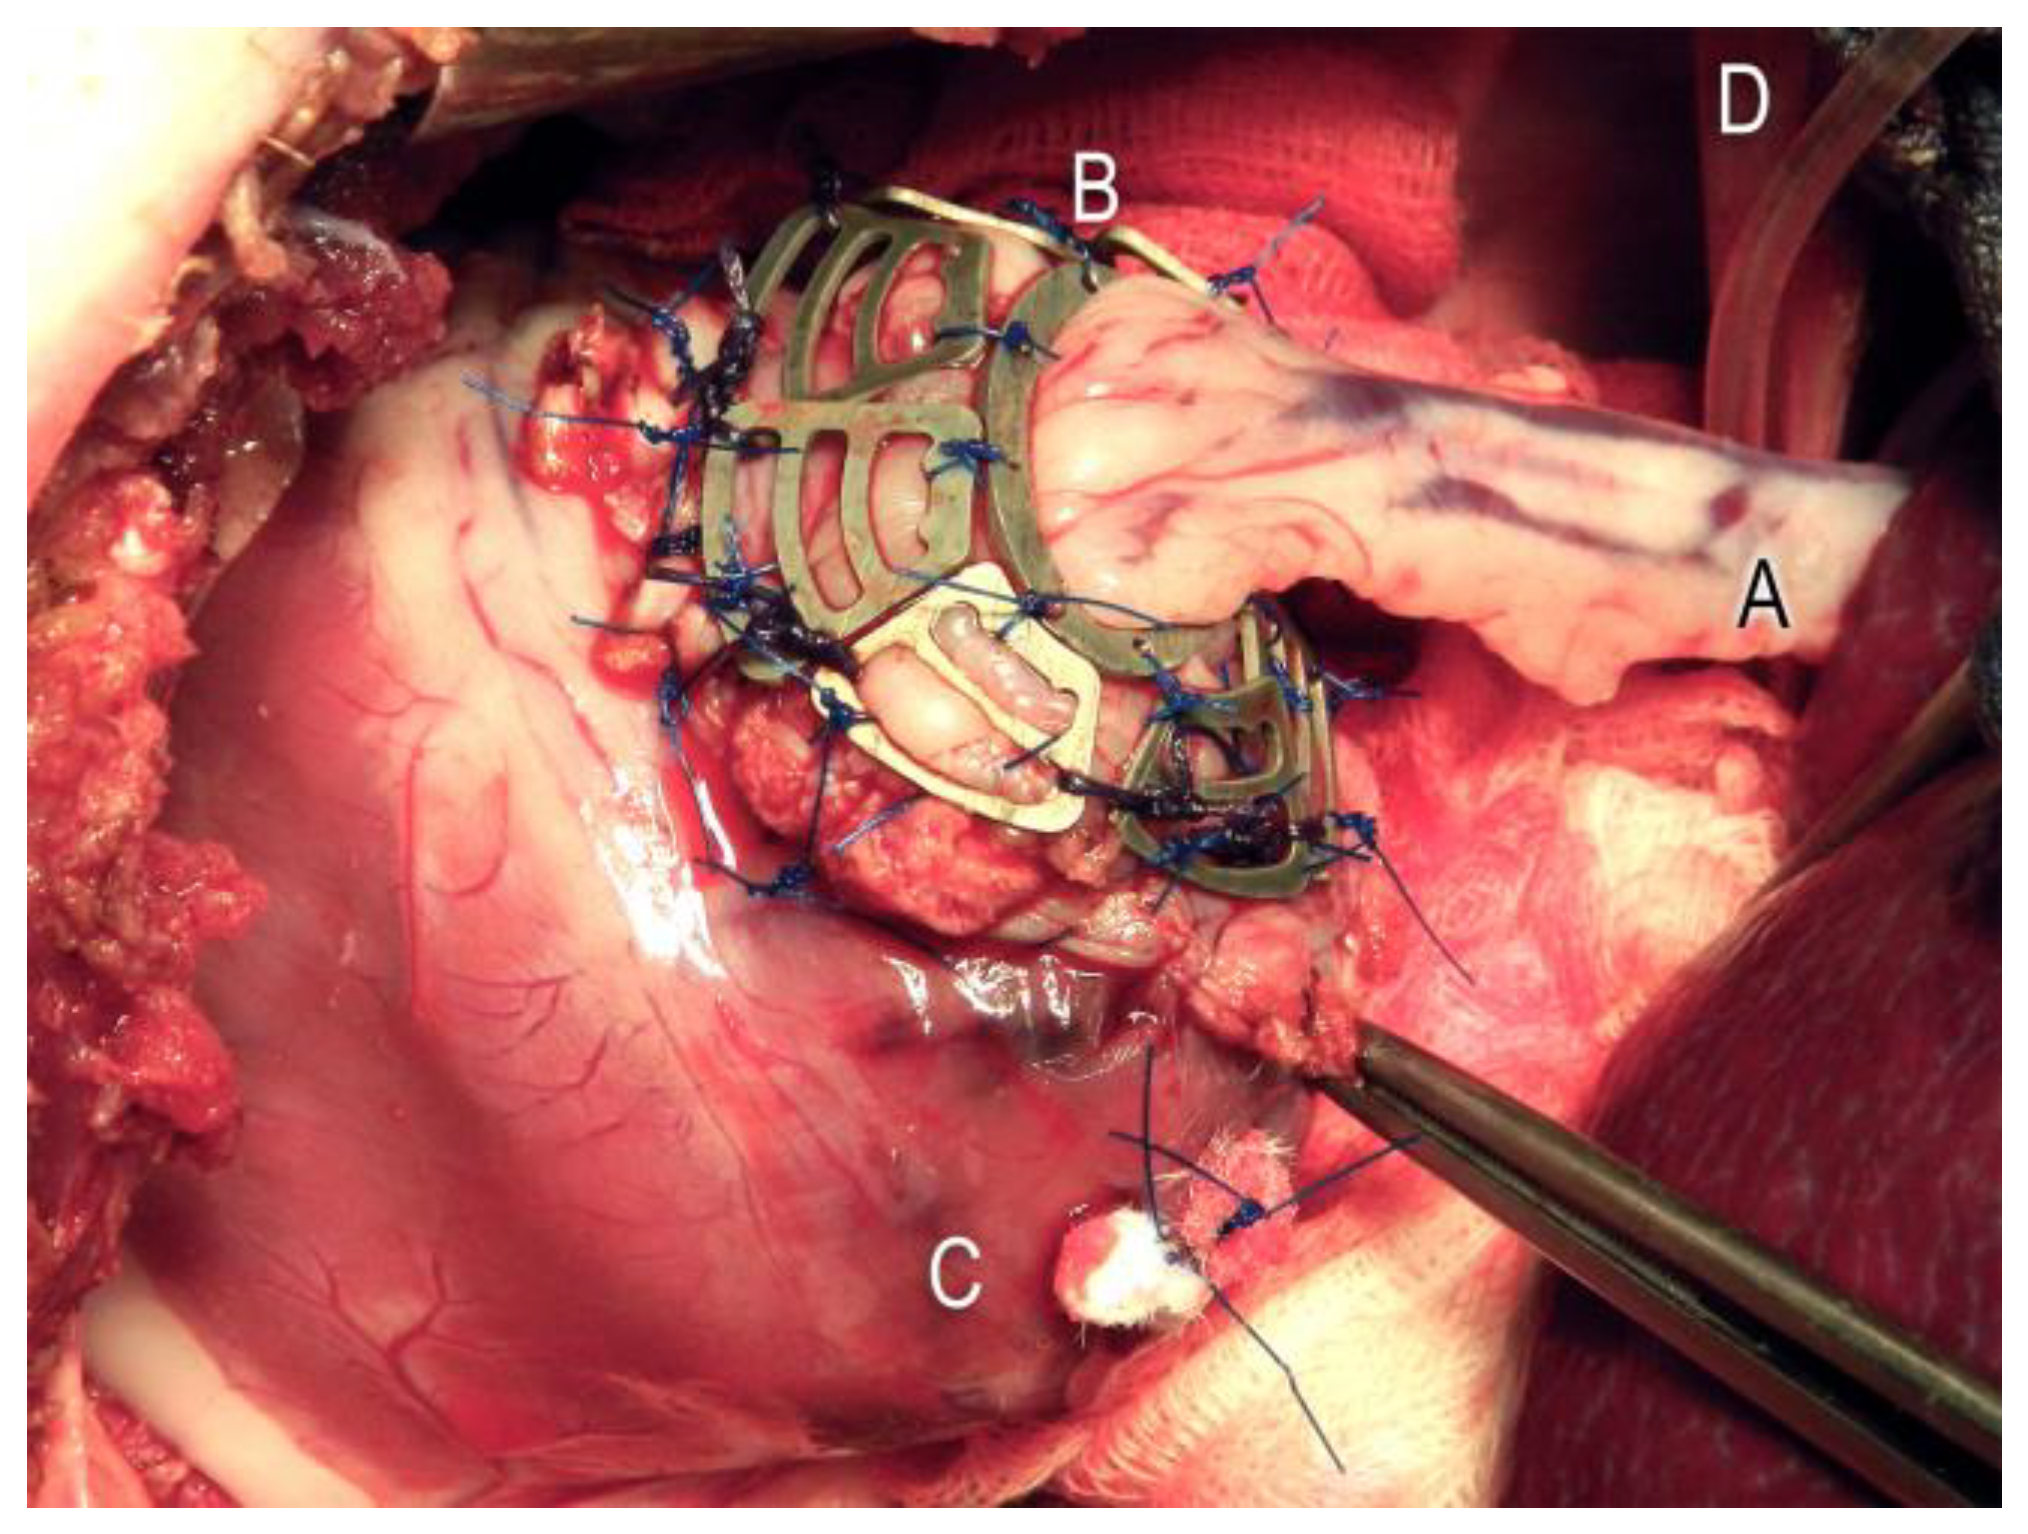

In the animals of the Mg group, nine segments of the magnesium scaffold were now epicardially fixed in the boundary zone between the myocardium and stomach tissue using single-button technology (Polyprolene 4.0, Ethicon, Germany) (see Figure 3).

Figure 3.

Nine epicardially fixed Mg segments (B) to stabilize the stomach patch (A) used to close the left ventricular (C) myocardium defect. Diaphragm (D).